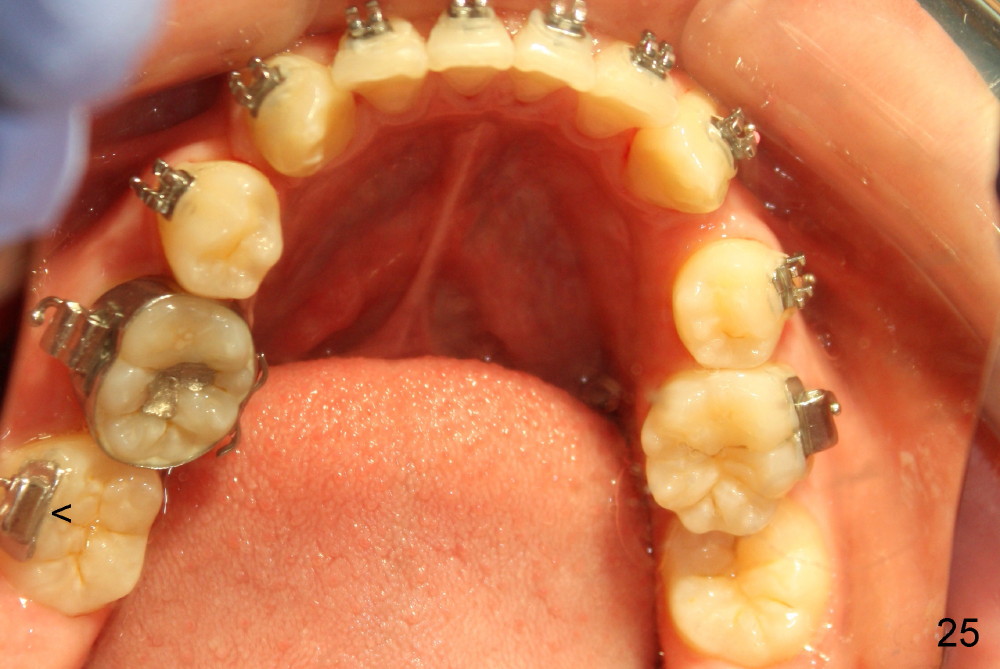

Four and a half months post bracketing (Fig.21-25), what do you find and what should be done next?

Prior to bracketing, the mesiodistal space for #18 is planned to be obtained by moving #20 and then #19 mesially (Fig.31-35, 16x16 ss). The six anterior lower teeth are tied together in a figure 8 fashion. Power chains are placed between the lower canine and the 2nd bicuspids. The upper diastemata are to be closed by power chains between the 1st molars.